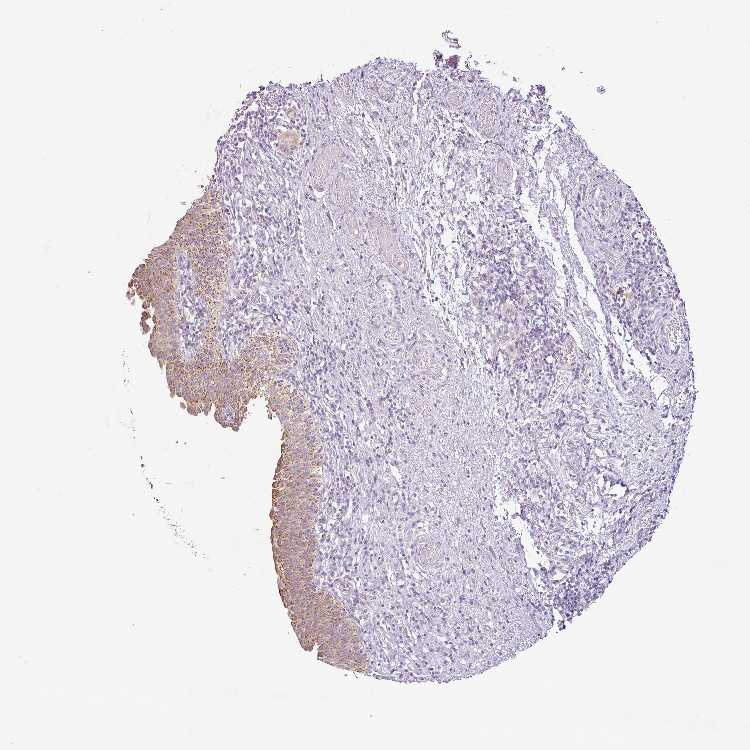

URINARY BLADDER - Antibody stainingi

Antibody staining in the annotated cell types in the current human tissue is reported as not detected, low, medium, or high, based on conventional immunohistochemistry profiling in selected tissues. This score is based on the combination of the staining intensity and fraction of stained cells.

Each image is clickable and will lead to virtual microscopy that enables deeper exploration of all samples and also displays staining intensity scores, fraction scores and subcellular localization as well as patient and tissue information for each sample.

Antibody HPA053903Antibody HPA070647

Urothelial cells MediumNot detected